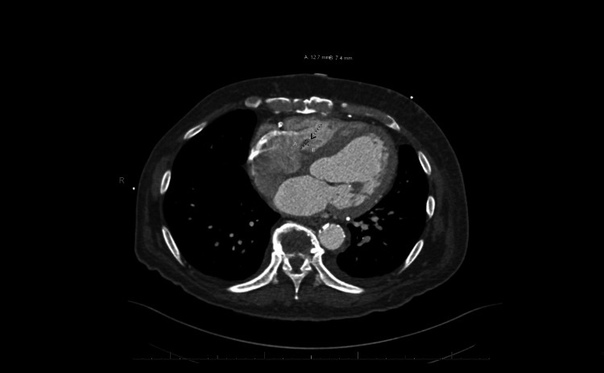

При осмотре: в толще барабанных перепонок пузырьки воздуха, признаков отека или воспаления нет. Аудиография: умеренная кондуктивная тугоухость справа, нормальный слух слева.